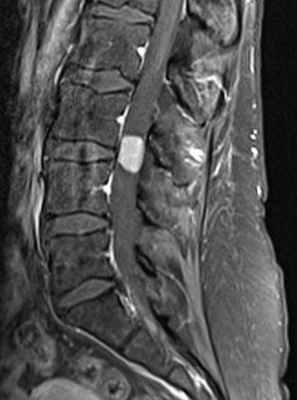

МРТ поясничного отдела позвоночника. Интрадуральная менингиома в поясничном отделе. Сагиттальная Т1-взвешенная МРТ после контрастирования.

Менингиомы составляют до 40% опухолей этой локализации и 25% от всех спинальных опухолей. Обычно диагностируются в возрасте около 40-50 лет. Редко спинальные менингиомы встречаются у детей (3-6% от всех случаев менингиом) как проявление нейрофиброматоза II типа. При этом заболевании менингиомы могут быть множественные, что составляет около 2% от случаев менингиом. Происходят менингиомы из паутинной оболочки. Они инкапсулированы, имеют широкое основание, хорошо васкуляризированы, часто содержат кальцинаты и редко подвергаются кистозной дегенерации. У женщин встречаются в 4 раза чаще, чем у мужчин. Растут они очень медленно. Интрадурально расположены 85% менингиом и около 6% экстра-интрадурально и около 7% – экстрадурально. Около 75 – 80% менингиом располагаются в грудном отделе позвоночного канала, 15 – 17% в шейном отделе, 3% – в поясничном и около 2% в области большого затылочного отверстия. Злокачественные спинальные менингиомы описаны в казуистических наблюдениях. Клинические проявления состоят из локальных болей в спине и миелопатическом синдроме при компрессии спинного мозга.

На Т1-взвешенных МРТ менингиомы изоинтенсивны спинному мозгу. На Т2-взвешенных МРТ фибробластные менингиомы, как правило, низкого сигнала, в то время как другие гистологические варианты обычно умеренно повышенного сигнала. Контрастирование при МРТ быстрое и равномерное, иногда охватывающее и прилегающую твердую мозговую оболочку (“дуральные хвосты”). По форме на сагиттальных и корональных МРТ позвоночника менингиомы обычно полукруглые, с широким основанием, обращенным к оболочке. Менингиомы четко очерчены при МРТ. Рост по типу “песочных часов” нетипичен.